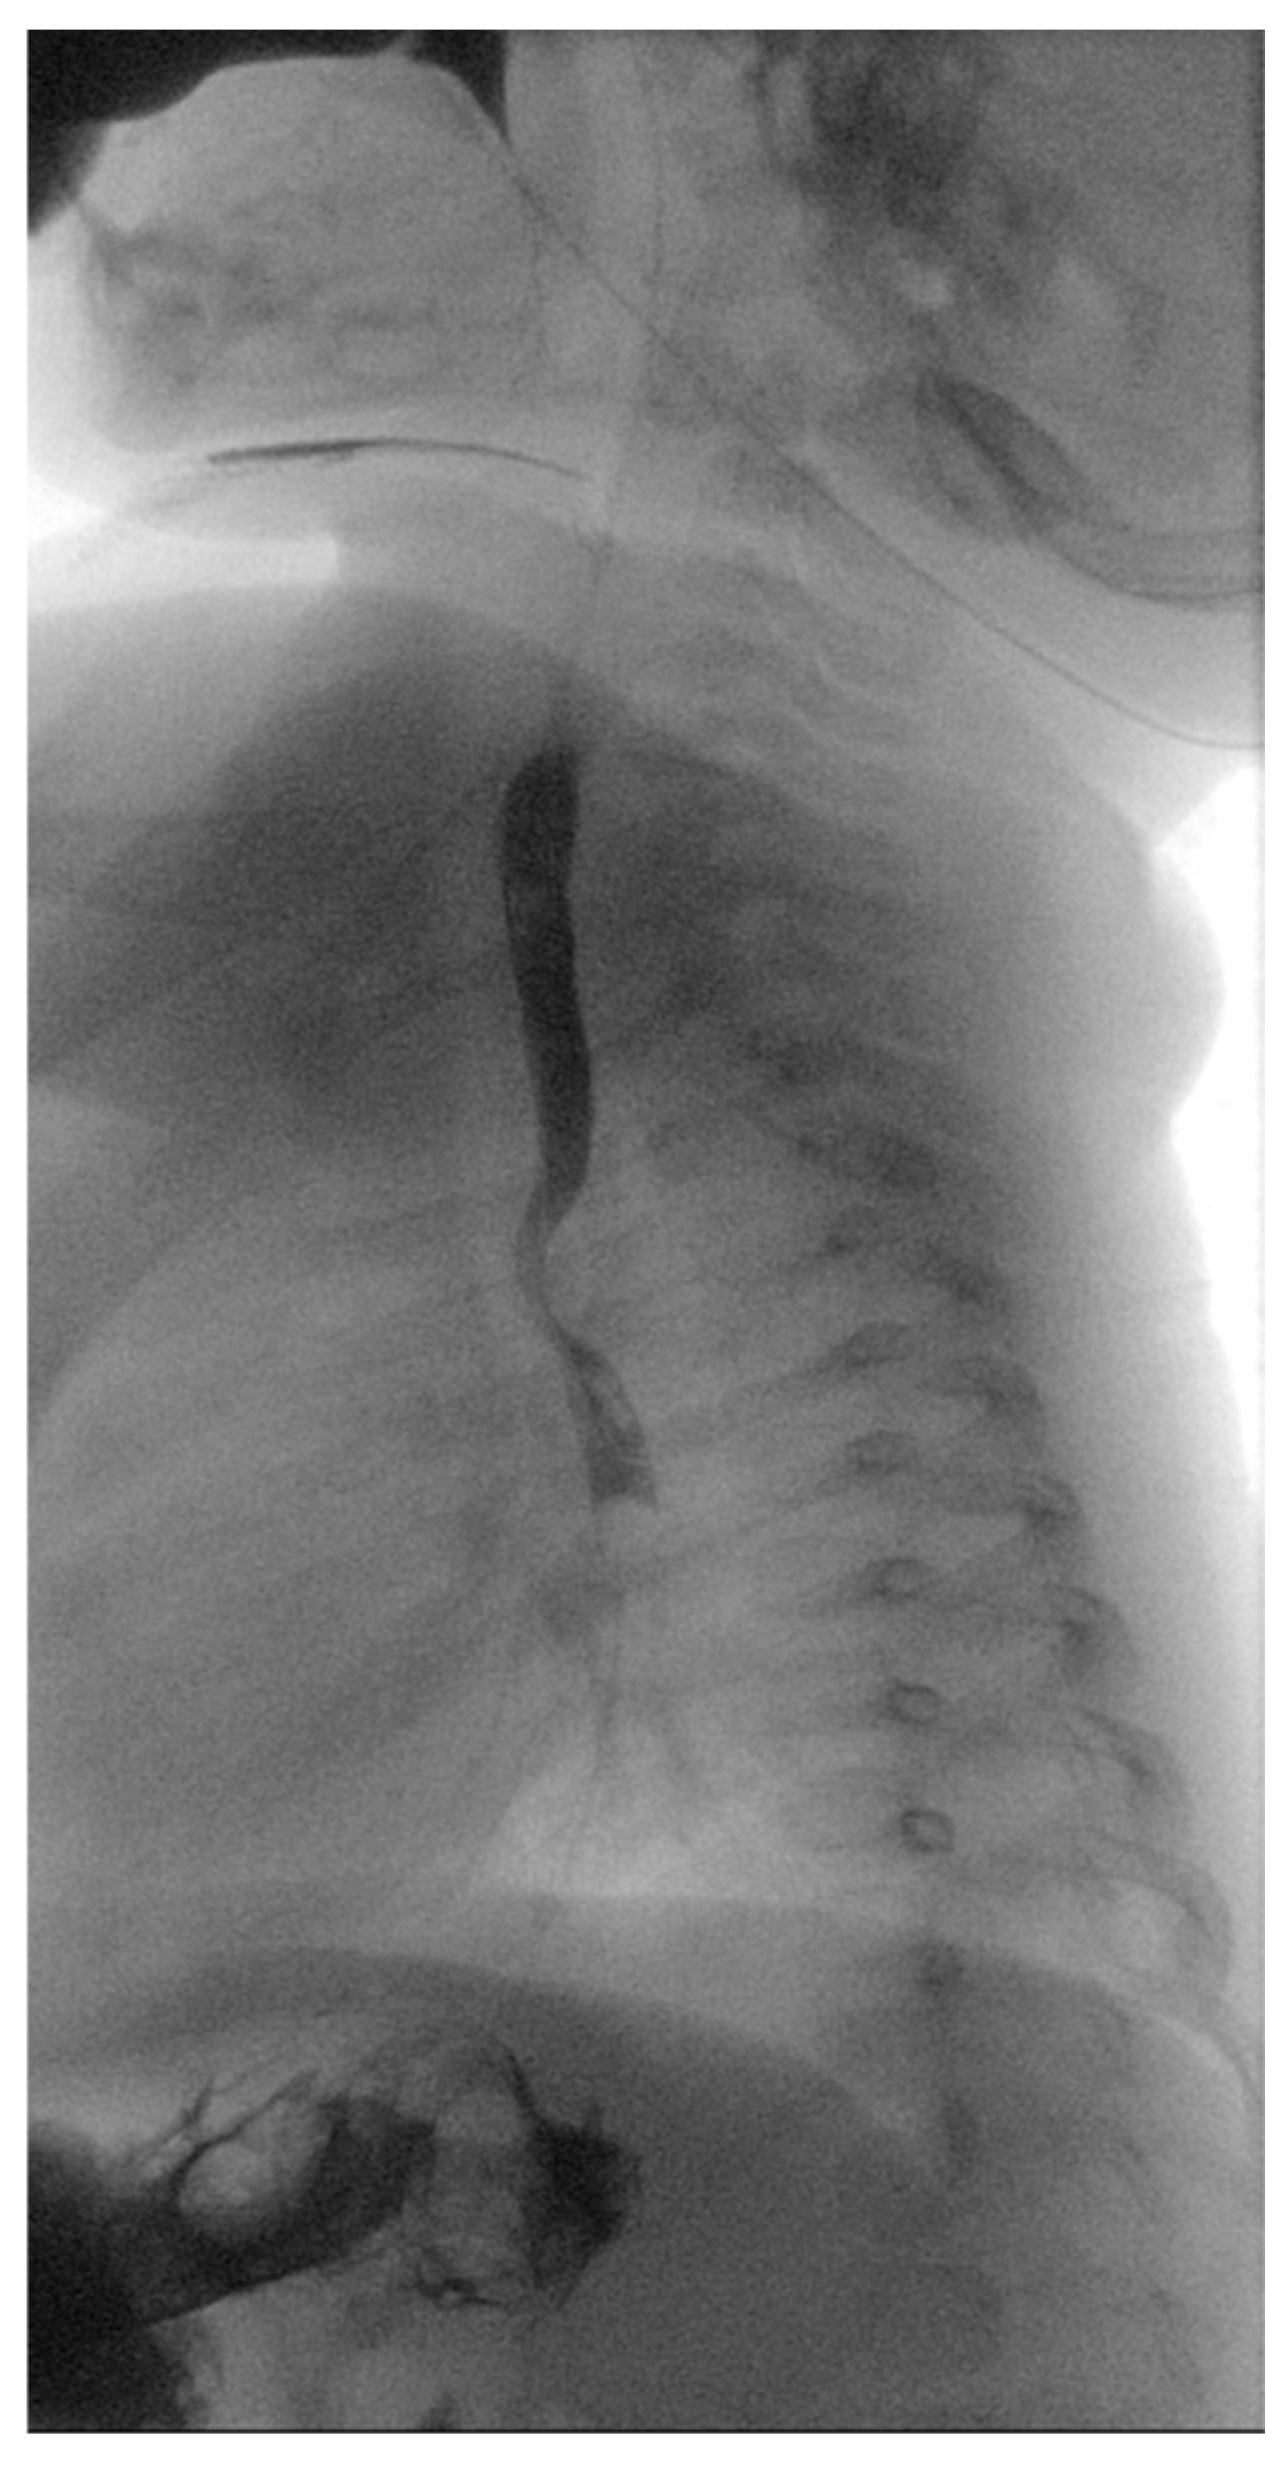

A 5-month-old female patient was being evaluated for failure to thrive secondary to dysphagia while on a liquid diet, requiring feeding aids (nasogastric tube). Past medical history accounts for in utero umbilical hemorrhage at 34 weeks’ gestation and intrauterine growth restriction, without any cardiovascular anomalies identified in fetal morphology scans. A barium swallow test was performed, which revealed a posterior indentation of the proximal thoracic esophagus (Figure 1).

Figure 1.

Barium swallow test. Posterior indentation of the proximal thoracic esophagus.